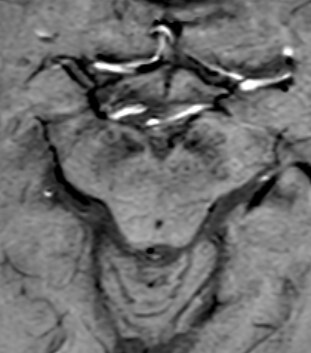

3T MRI offers significantly better contrast for neuromelanin imaging, along with moderate sensitivity for detecting iron deposition. The “swallow tail” sign is typically present in healthy individuals but disappears in patients with PD, making it a simple and practical marker in everyday clinical use [14] (Figure 1).

In MSA, MRI typically reveals atrophy of the cerebellum, brainstem, and putamen, as well as characteristic signal abnormalities. The so-called “hot cross bun sign” in the pons and hyperintense lateral putaminal rims on T2W images are highly suggestive of MSA-C and MSA-P phenotypes, respectively [26] (Figures 2 and 3).

A, B, C, D Midbrain morphometry. MRI axial FLAIR A) Line expresses the transverse diameter of the midbrain at the the level of the superior colliculus B) The thickness of the superior cerebellar peduncle at the level of the inferior colliculus C) Thickness of the inferior cerebellar peduncle D) Transverse diameter of the medulla oblongata at the level of the inferior olivary nucleus

Measuring the pons and midbrain area. FLAIR sagittal image. Elliptical regions of interest were placed over the pons and the midbrain in the midsagittal slice

In PSP, midbrain atrophy with preserved pons volume (leading to the “hummingbird sign” or “morning glory sign” in sagittal view) is a classic imaging finding (Figure 4). Volumetric studies have identified reductions in midbrain tegmental area and superior cerebellar peduncles as robust MRI biomarkers [27].